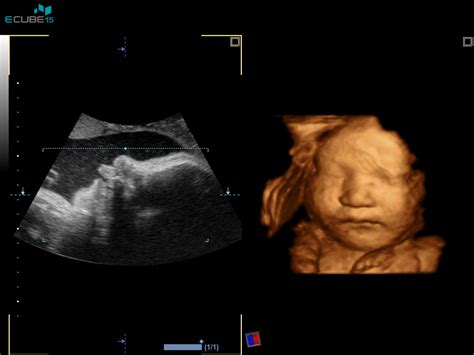

V 26. tednu nosečnosti otrok že dobro razvija svoje motorične sposobnosti. Dolg je približno 35-36 cm, kar je primerljivo z velikostjo buče špagetarice. V tem tednu se odprejo otrokove nosnice, kar pomeni, da lahko prvič "vdihne" plodovnico, s čimer se intenzivno urijo pljuča vse do rojstva. Prav tako se v tem obdobju razvije otrokov vid, saj so njegove oči že povezane z možganskimi predeli, ki so odgovorni za obdelavo vizualnih dražljajev.

Posledično postajajo gibi otroka v 26. tednu vse bolj opazni in raznoliki. Lahko zaznate brce, premikanje rokic, obračanje ali celo rahlo ritmično trzanje, ki ga povzroča krčenje diafragme ploda - znano kot "štucanje". Te gibi lahko postanejo še posebej izraziti, ko se nosečnica umiri, na primer zvečer ali med počitkom, saj takrat lažje zazna aktivnost otroka. Prav tako se lahko aktivnost poveča po obroku, kar je povezano z dvigom ravni sladkorja v krvi, ki vpliva na otrokovo energijo.